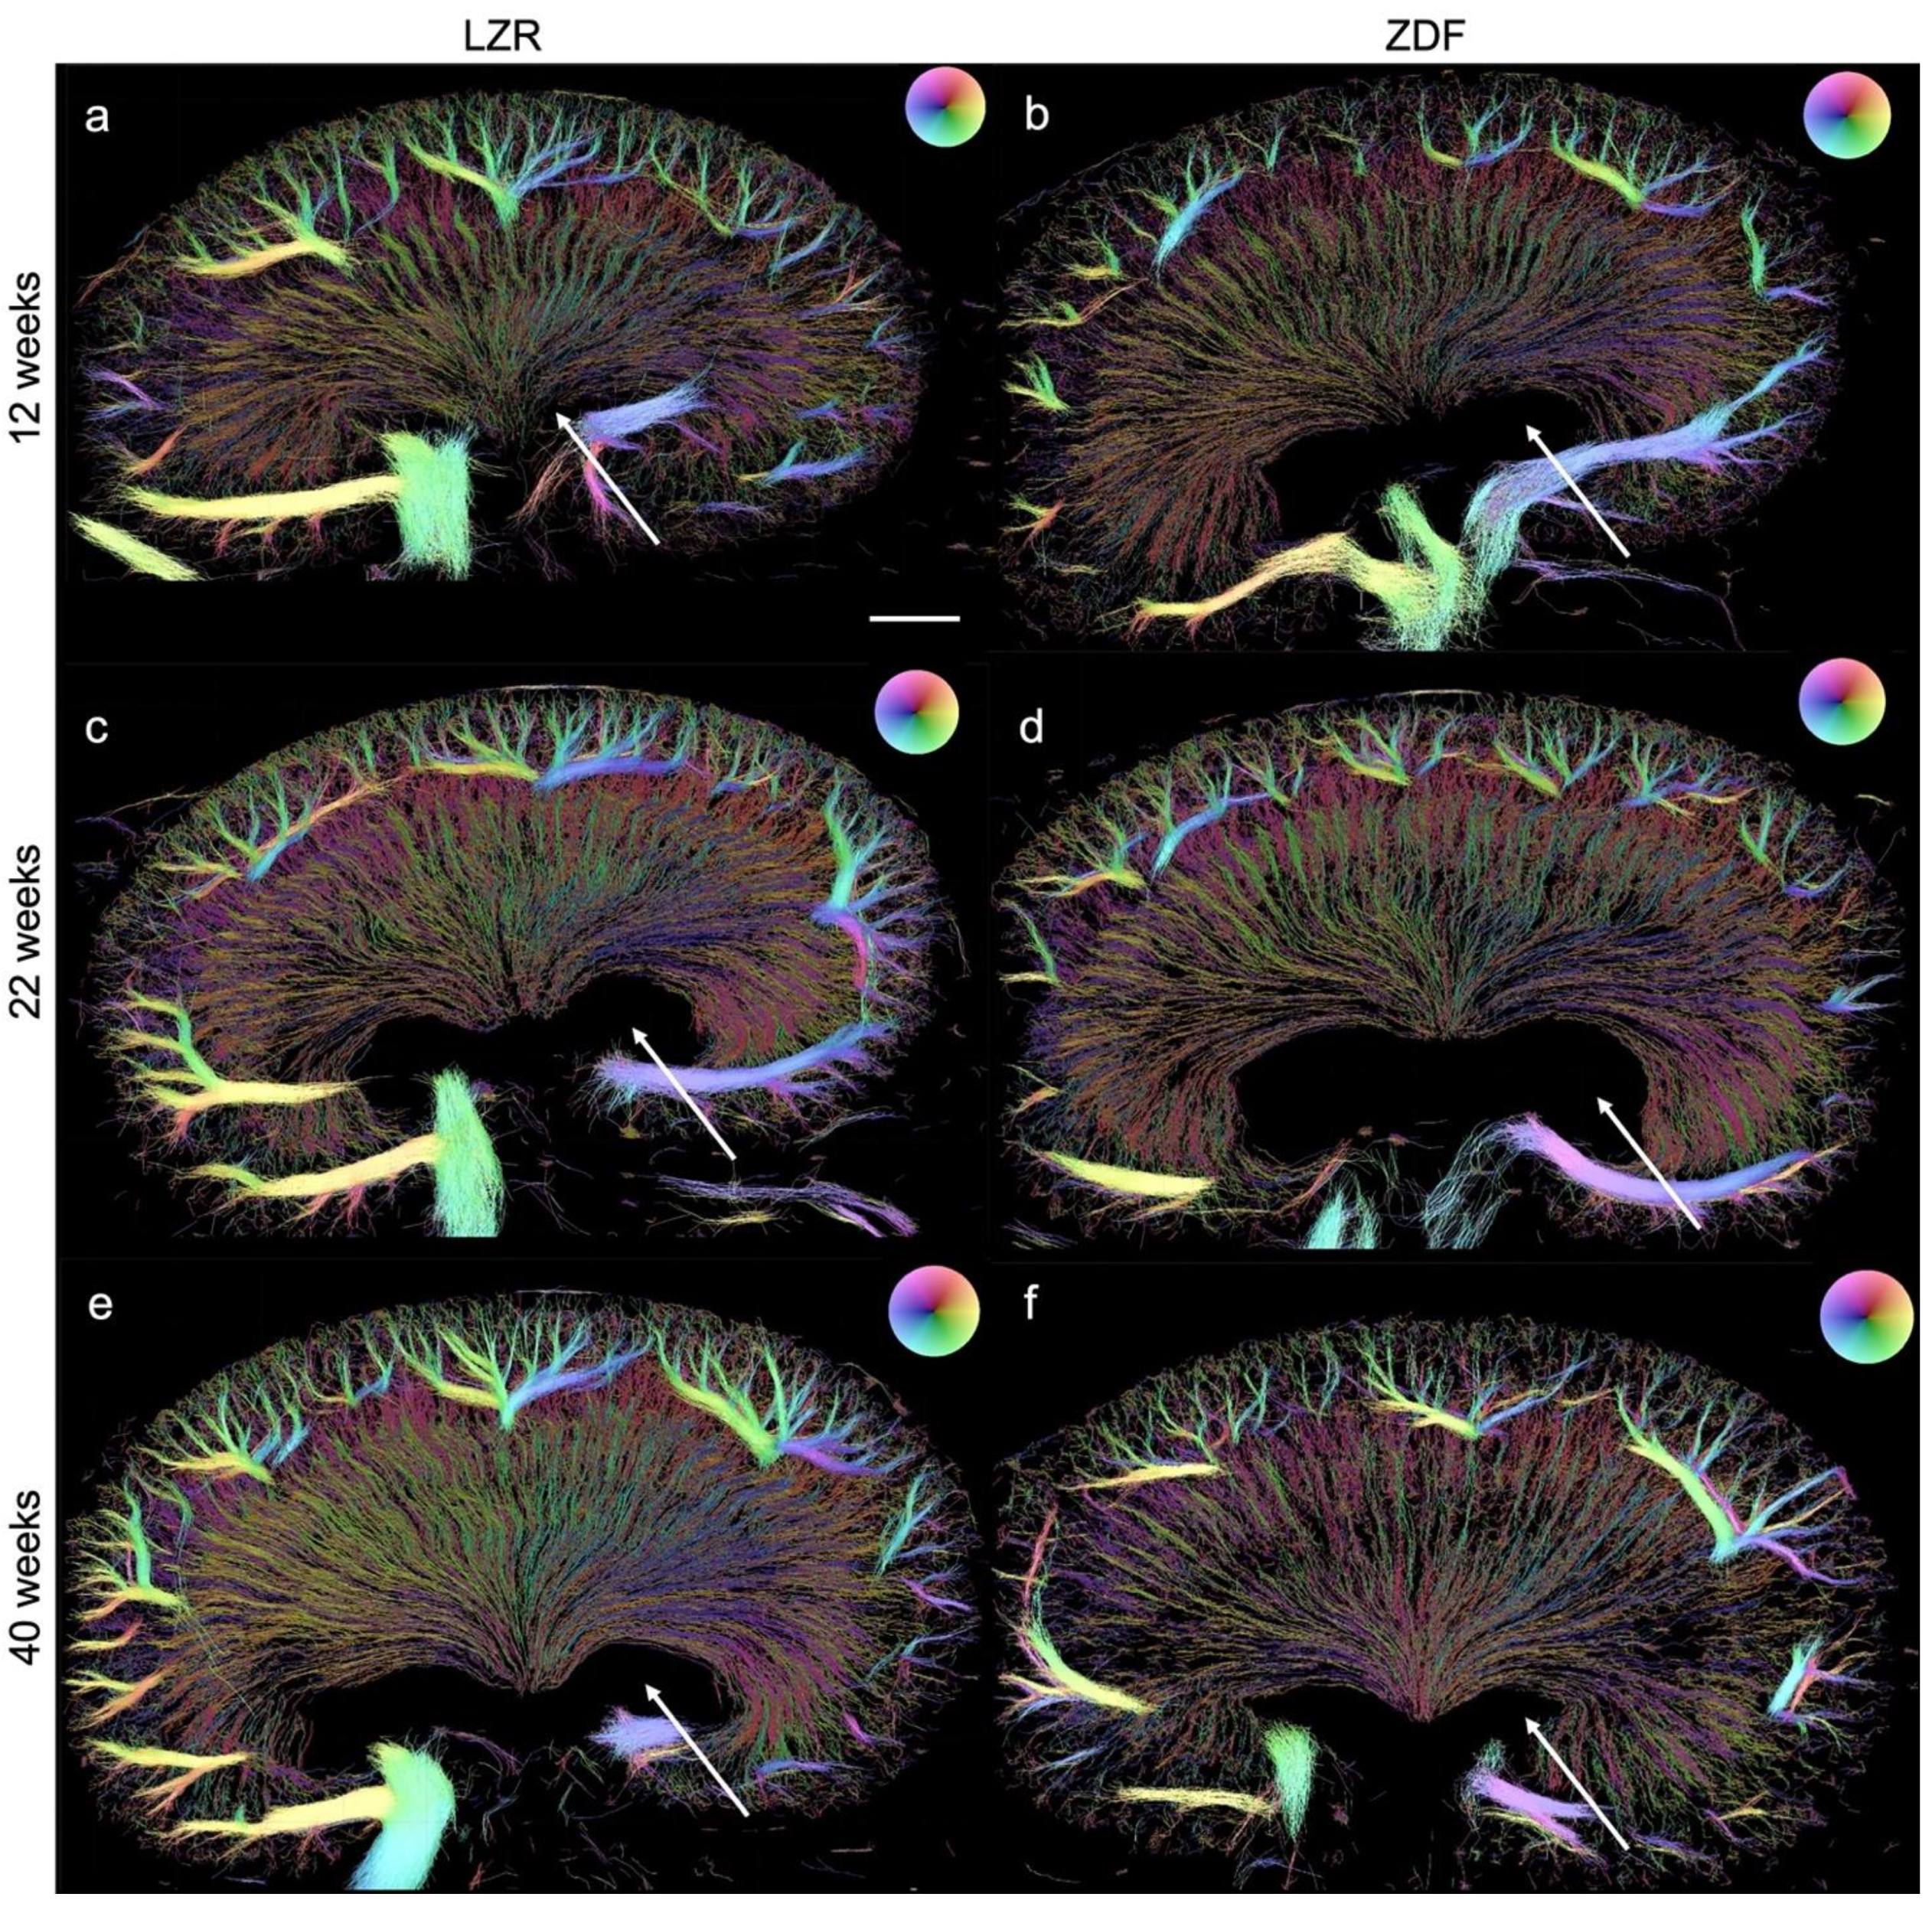

3.3. Quantified Measurements from SRUS

3.4. Qualitative and Quantitative Assessment in µCT